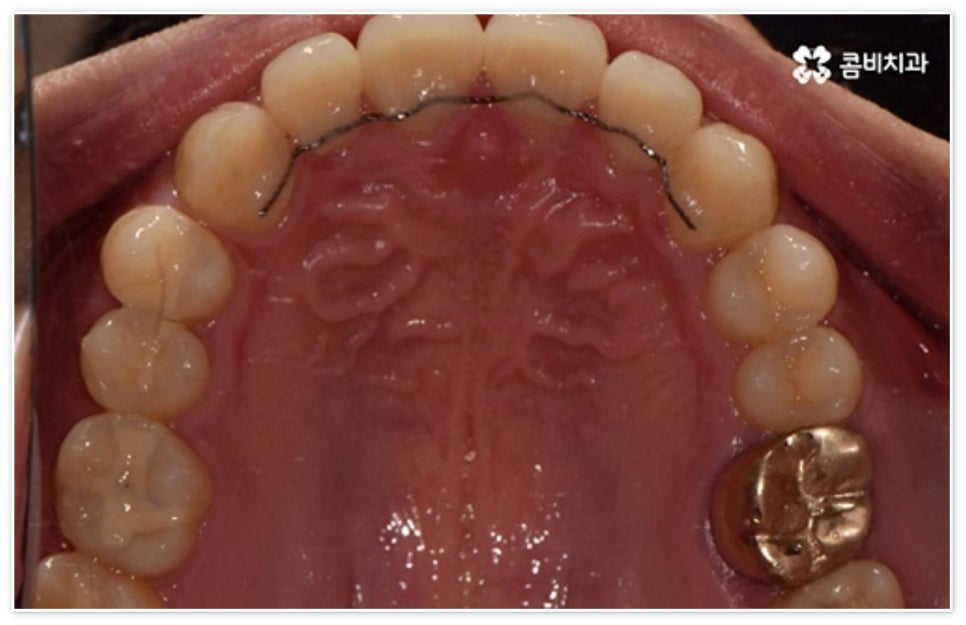

환자분들에 따라 다르지만 통상적으로 전체 교정이 1년에서 2년 반 정도 소요된다면 부분 교정은 6~8개월 정도로 기간 단축이 가능하여 치료에 대한 부담을 줄일 수 있으며 대부분 발치 과정 없이 필요한 부위에만 브라켓을 부착하는 만큼 불편함이 적고 구강 관리도 용이한 편이니 (사진에서 살펴볼 수 있는 케이스) 이에 대해서 자세히 알아보시면 좋을 거예요. 물론 누구나 가능한 것은 아니고 개인의 구강 상태에 따라 진행을 해야 하므로 꼼꼼한 검진과 충분한 상담부터 받아보시길 권유드리고 있습니다.